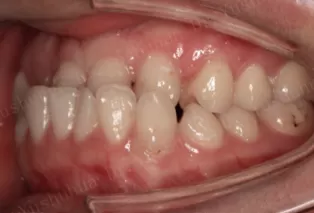

Photos intra-orales